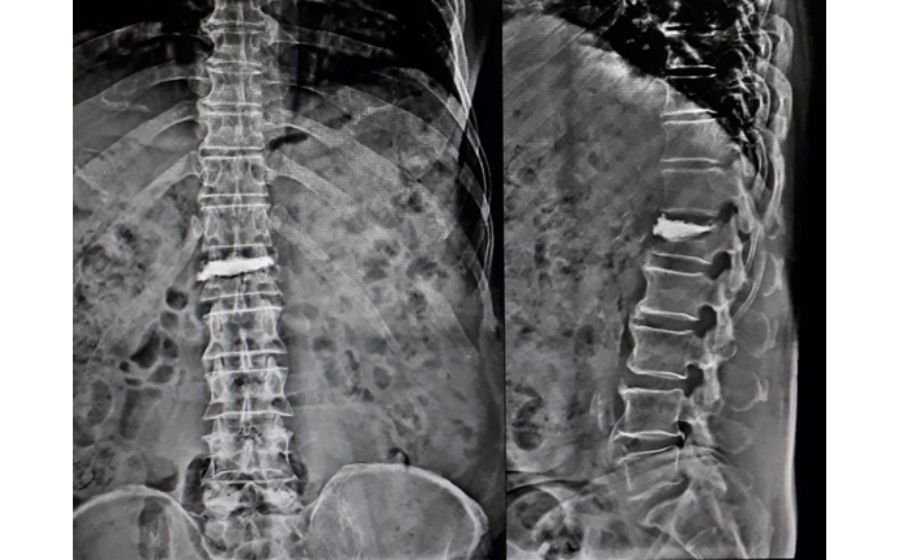

Scoliosis Surgery

Scoliosis surgery is performed when a spinal curve becomes severe enough to affect posture, balance, breathing, or overall comfort. The procedure straightens and stabilizes the spine using screws and rods, allowing the bones to fuse in a corrected position. Throughout the surgery, advanced neuromonitoring is used to continuously check the function of the nerves and spinal cord, adding an extra layer of safety and ensuring precise, protected correction. The goal is to restore alignment, prevent curve progression, and help patients stand straighter and return confidently to daily life.